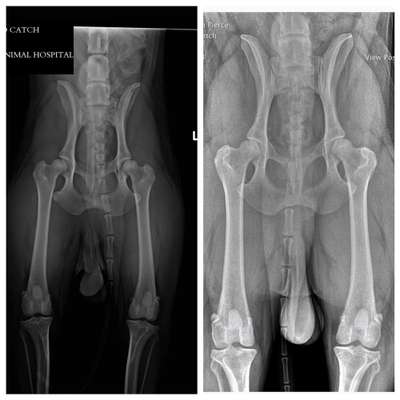

Ich pack mal zwei “exzellente” Hüften hier rein, Pudel und Mali

Man sieht, wie schön bedeckt der Knochenkopf ist von der Hüftpfanne und wie symmetrisch und rund die sind

Im Vergleich zu dem anderen Bild erkennt man auch die Fehllagerung gut, richtig?

Hier ist der Femurkopf weitaus höher als der „andere Knubbel“ (dessen Namen ich nicht kenne)